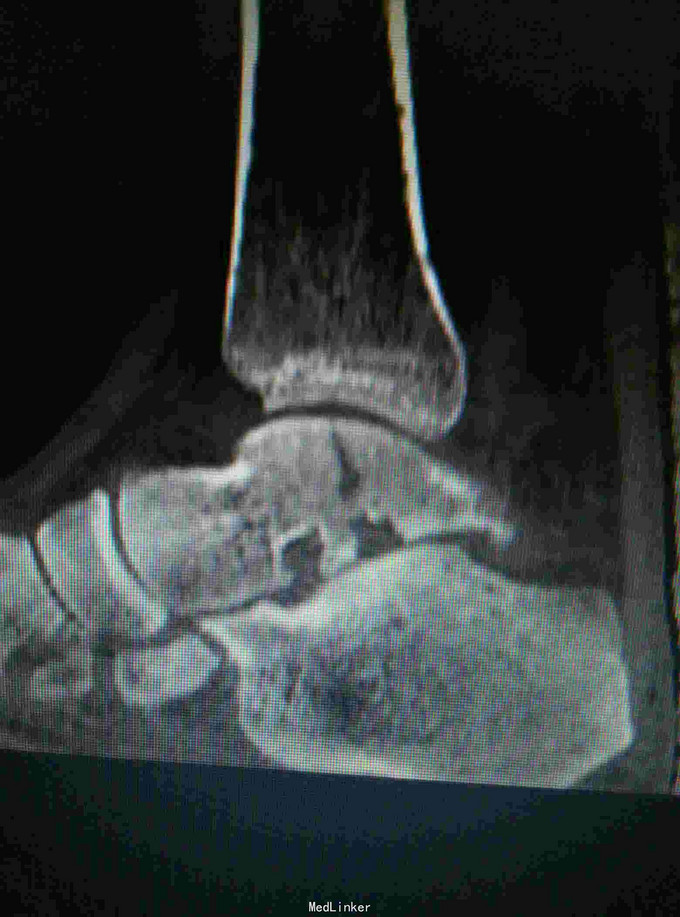

诊断是右距骨粉碎性骨折。给予行内踝截骨显露骨折端进行复位,采用Herbert钉进行固定。

术后复查X线片提示骨折端完全复位,内固定固定在位良好。 讨论:距骨骨折的主要并发症是坏死,骨不愈合等,但近年来随着对其认识的不断明确,治疗比较规范,积极的进行切开复位,并行坚强固定,近年的研究报告提示距骨的坏死率是不断在下降的,当然前提是进行有效复位并坚强固定。